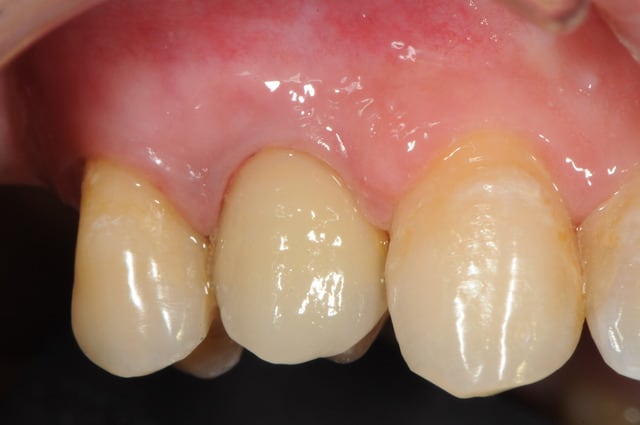

le hasard fait parfois bien les choses...patient revu ce matin pour une "bricole" sur une restauration postérieure...

il est intéressant de voir la maturation des tissus mous...et en plus VS des différences au niveau de l'hygiène, pas mal secteur 2 mais perfectible secteur 1...

ici on est à 3 mois post pose prothèses d'usage...la photo, prise un peu décalée, donne l'impression d'une différence de hauteur des collets, mais il n'en est rien (ou alors très peu...)

quand même content du résultat...;-) même si j'ai (lourdement)insisté pour que l'hygiène soit un peu mieux suivie...